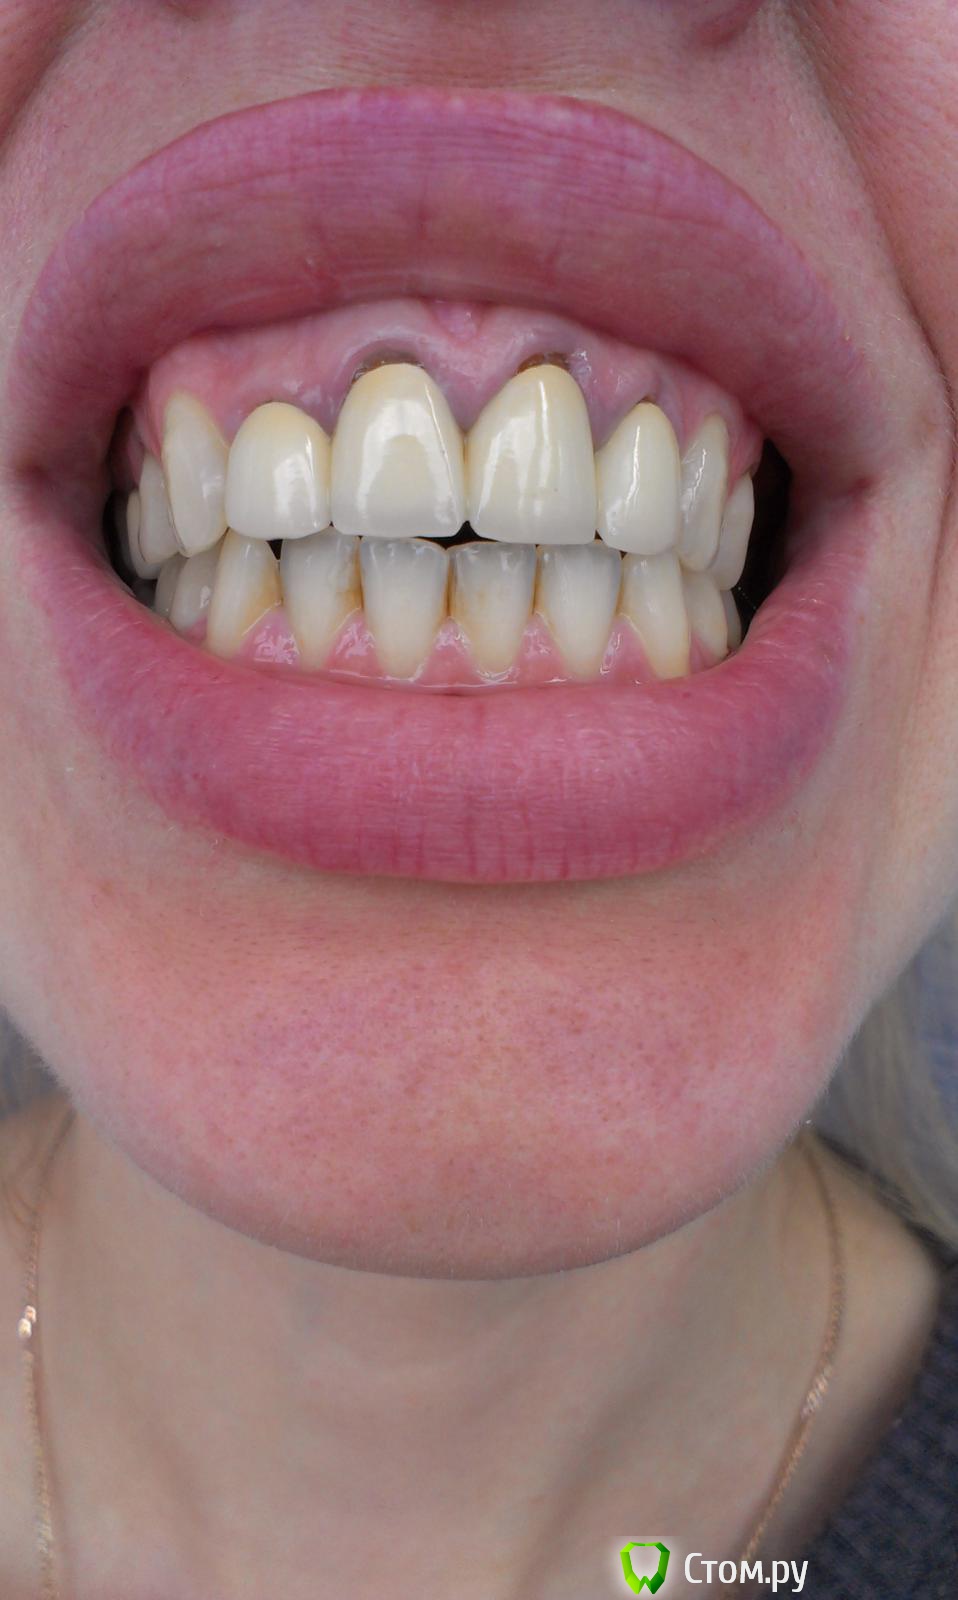

Ольга97-99 Опубликовано 6 сентября, 2014 Поделиться Опубликовано 6 сентября, 2014 Добрый день, уважаемые стоматологи. Прошу помощи... Ситуация с зубами плачевная... Не буду долго расписывать о том, как с 10 лет я не вылезаю из кресла стоматолога. Леченые зубки в небольном городе Н. Постоянно выпадающие пломбы, приводящие к повторному лечению. Депульпированны практически все. Периодичность посещения стоматолога - 3 мес., + манипуляции парадонтолога. Но к 26 годам имеем нижепредставленное.. С задними зубами все более или менее ясно - еще несколько на удаление, затем имплантация. С передними верхними... МК коронкам 7лет. Не беспокоят, боли, дискомфорта нет. Но эстетика оставляет желать лучшего. Еще, как говориться, не везет так не везет - улыбка десневая. И поднявшаяся синюшная десна во всю сияет. Было решено - настало время перемен. Мой обход ортопедов в нашем славном городе начался с мыслью вдохновляющей "заменить мк на дц". Более натуральный вид, к тому же рецессия десны должна была остановиться, так Интернет и доктора говорили )). Что имеем сейчас, мнения двух (на мой взгляд самых адекватных спецов) ортопедов: Первый: снимаем коронки, смотрим состояние корней. Если все нормально, штифты не трогаем, меняем пломбы и делаем дц. Но 80-90% вероятность, что корни испортились, либо будут повреждены (при снятии коронки выйдет штифт, разрушив корень). Тогда удаление, затем имплантация. Не буду портить мнение о себе и писать, что я испытывала после такого вердикта.... Второй: (его, кстати, посоветовал 1й) глянул (бегло) на мой снимки, говорит: снимаем коронки, вынимаем штифт, лечим каналы, делаем вкладки из дц, делаем коронки из дц. На мой вопрос "а если корень поврежден? или еще что-то не так пойдет" был ответ "зачем тебе это все знать, я доктор и я говорю тебе - будут коронки нормальные". Думаю, не стоит уточнять, что гарантий по сроку службы новых коронок я не услышала. Ну верней, прозвучала классика про кирпич на голову. Понятно, какой вариант мне запал в душу, и чего я бы хотела.. Но я могу хотеть одного, а реальность может быть совсем другой.. Не имею право на неоправданный риск, это же передние зубы... Пожалуйста, посмотрите снимки. Можно услышать Ваше мнение насчет возможности замены протезов передних верхних зубов. Заранее спасибо!!! Ссылка на комментарий

m.d.n Опубликовано 7 сентября, 2014 Поделиться Опубликовано 7 сентября, 2014 Спасибо! Консультация парадонтолога - по состоянию десен? с вашей линие й улыбки- чтобы сделать тут красиво - надо провести немалую работу. нужен хороший ортопед и пародонтолог . Ссылка на комментарий

Bier Опубликовано 7 сентября, 2014 Поделиться Опубликовано 7 сентября, 2014 Если хочется красиво, нужно будет еще с десневым краем работать 1 Ссылка на комментарий

Bier Опубликовано 7 сентября, 2014 Поделиться Опубликовано 7 сентября, 2014 значит комплексного подхода нет, если хотите красиво, а не забор - ищите дальше. Ссылка на комментарий